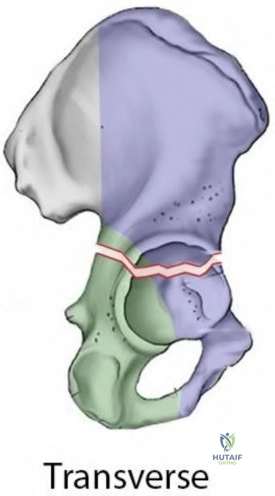

A 72-year-old male with a history of a cemented total hip arthroplasty (THA) 15 years ago presents with persistent groin pain and aseptic loosening of the acetabular component. Radiographs show significant acetabular osteolysis and a Paprosky Type IIIB defect.

Which of the following is the MOST appropriate reconstructive option for this acetabular defect?